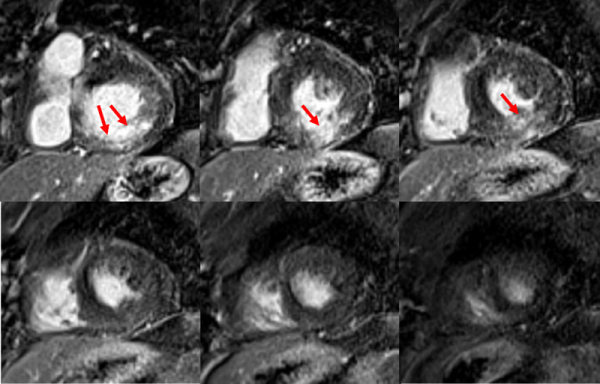

Figure 7A : Séquence de rehaussement tardif

Coupes petit-axe

Figure 7B : Séquence de rehaussement tardif

Coupes long-axe 4 cavités et 2 cavités

Présence d’un rehaussement tardif sous-endocardique (flèches rouges) correspondant à une séquelle d’IDM inféro-latéral viable avec transmuralité < 50% d’épaisseur (correspond à la séquelle d’IDM inféro-latéral déjà connue en 2011 chez la patiente).

Bonus « le coup d’œil de l’imageur » : Fils de sternotomie

Vous pouvez voir sur l’image la présence d’artéfacts métalliques (flèches bleues) correspondant aux fils de sternotomie Important de noter que ces artéfacts ne posent aucun problème pour l’interprétation des images d’IRM cardiaque.